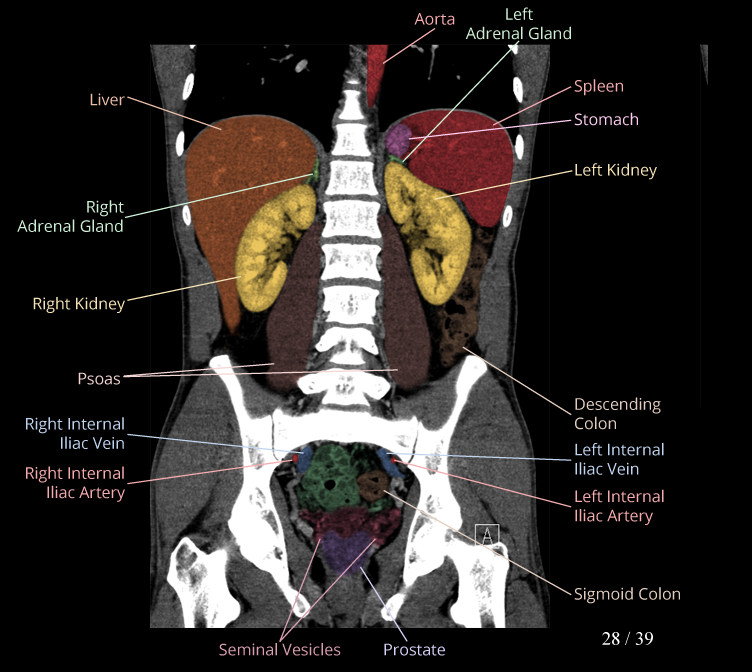

Body

Covers abdominal CT anatomy.